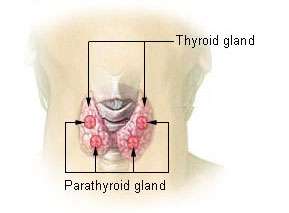

Numerous animal studies have demonstrated an association between endocrine disrupting chemicals (including BPA) and obesity.[3][55] However, the relationship between bisphenol A exposure and obesity in humans is unclear.[56] Proposed mechanisms for BPA exposure to increase the risk of obesity include BPA-induced thyroid dysfunction, activation of the PPAR-gamma receptor, and disruption of neural circuits that regulate feeding behavior.[56][57] BPA works by imitating the natural hormone 17B-estradiol. In the past BPA has been considered a weak mimicker of estrogen but newer evidence indicates that it is a potent mimicker.[58] When it binds to estrogen receptors it triggers alternative estrogenic effects that begin outside of the nucleus. This different path induced by BPA has been shown to alter glucose and lipid metabolism in animal studies.[59]

Thyroid function

A 2007 review concluded that bisphenol-A has been shown to bind to thyroid hormone receptor and perhaps has selective effects on its functions.[61]

A 2009 review about environmental chemicals and thyroid function raised concerns about BPA effects on triiodothyronine and concluded that "available evidence suggests that governing agencies need to regulate the use of thyroid-disrupting chemicals, particularly as such uses relate exposures of pregnant women, neonates and small children to the agents".[62]

A 2009 review summarized BPA adverse effects on thyroid hormone action.[63]